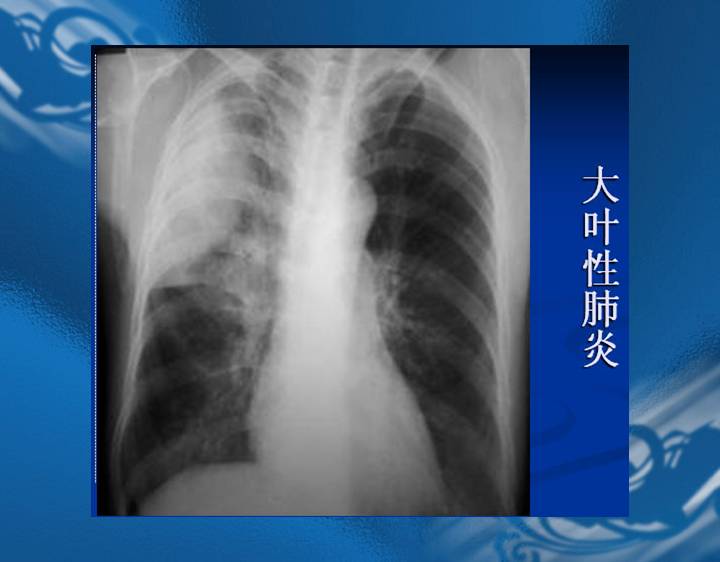

执业医师资格考试“实践技能”影像学辅导资料